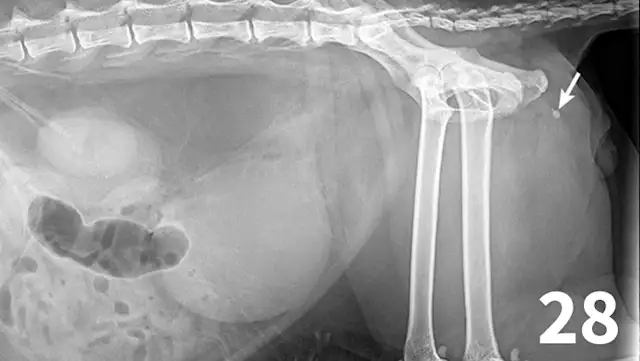

Figure 28.

There are 1 small and 1 large round urethral calculi (arrow) in this cat with urinary obstruction. The bladder is severely distended, and there is decreased detail caudal to the bladder. This demonstrates the importance of including the entire urethra on radiographs when urinary bladder obstruction is present or suspected.